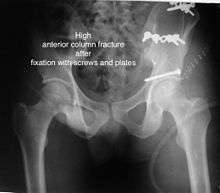

Anterior column fracture

Cause: Occurs when the force applied from the side. On the greater trochanter of the femur bone, as in fall on the side or being hit on the side

Types: Depending on the location, the fractures are described as very low, low, intermediate and high anterior column fracture.

How to diagnose: Best seen in Obturator oblique view

If the fragments do not fall into place, or if there are bone pieces in the joint, or if the joint is unstable, surgical fixation using screw(s) and plate(s) is performed